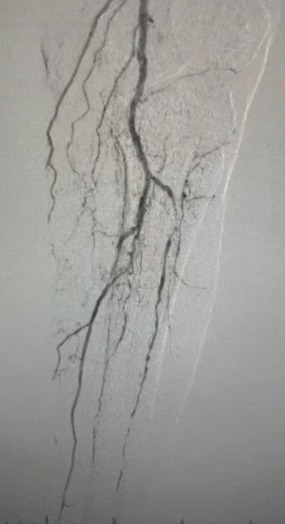

Résultats cliniques

· Examen physique: Impulsions fémorales faibles; pulsations absentes de poplité et de dorsalis pedis; ulcération sur le premier orteil gauche; nécrose sur le premier et le deuxième orteils droits

· Imagerie préopératoire: sténose calcifiée diffuse sévère dans les artères bilatérales des membres inférieurs

Résultat chirurgical

Après la procédure, la sténose artérielle s'est améliorée de manière significative, le flux sanguin a augmenté et la température de la peau a augmenté. Aucune complication postopératoire n'est survenue. Le patient et l'équipe chirurgicale étaient très satisfaits des résultats.